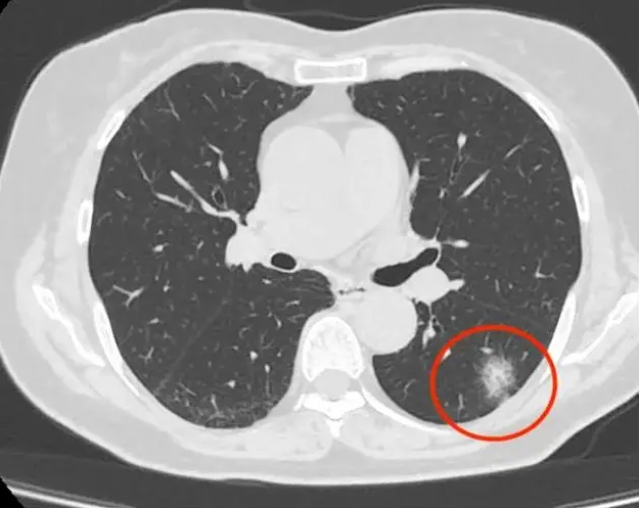

1 肺部感染性疾病 肺炎由病原微生物引起的肺部感染,X线表现为片状阴影,伴有咳嗽咳痰发烧等症状 肺结核由结核杆菌引起的肺部感染,阴影表现为散在的片絮状或球形病灶,患者常有咳嗽咯血及结核中毒症状 支气管扩张支气管壁的化脓性感染,X线表现为肺纹理增多增粗紊乱,严重时可。

肺部阴影是影像学检查如CT或X光中发现的肺部异常密度区域,可能由多种疾病引起,需结合进一步检查明确性质1 肺部炎症常见于细菌病毒或支原体感染引发的肺炎炎症导致肺部组织充血水肿,形成片状或斑片状阴影,多伴有发热咳嗽咳痰等症状及时使用抗生素或抗病毒药物后,阴影通常可逐渐吸收2。

肺部出现白色阴影可能是多种疾病的表现,常见原因包括肺炎肺结核肺癌和肺水肿,具体如下肺炎由细菌病毒或真菌等病原体感染肺部引发炎症影像学上,白色阴影通常因肺泡内充满炎性渗出物如脓液细胞碎片而形成,表现为片状或斑片状密度增高影患者常伴咳嗽发热呼吸困难等症状,血常规可能。